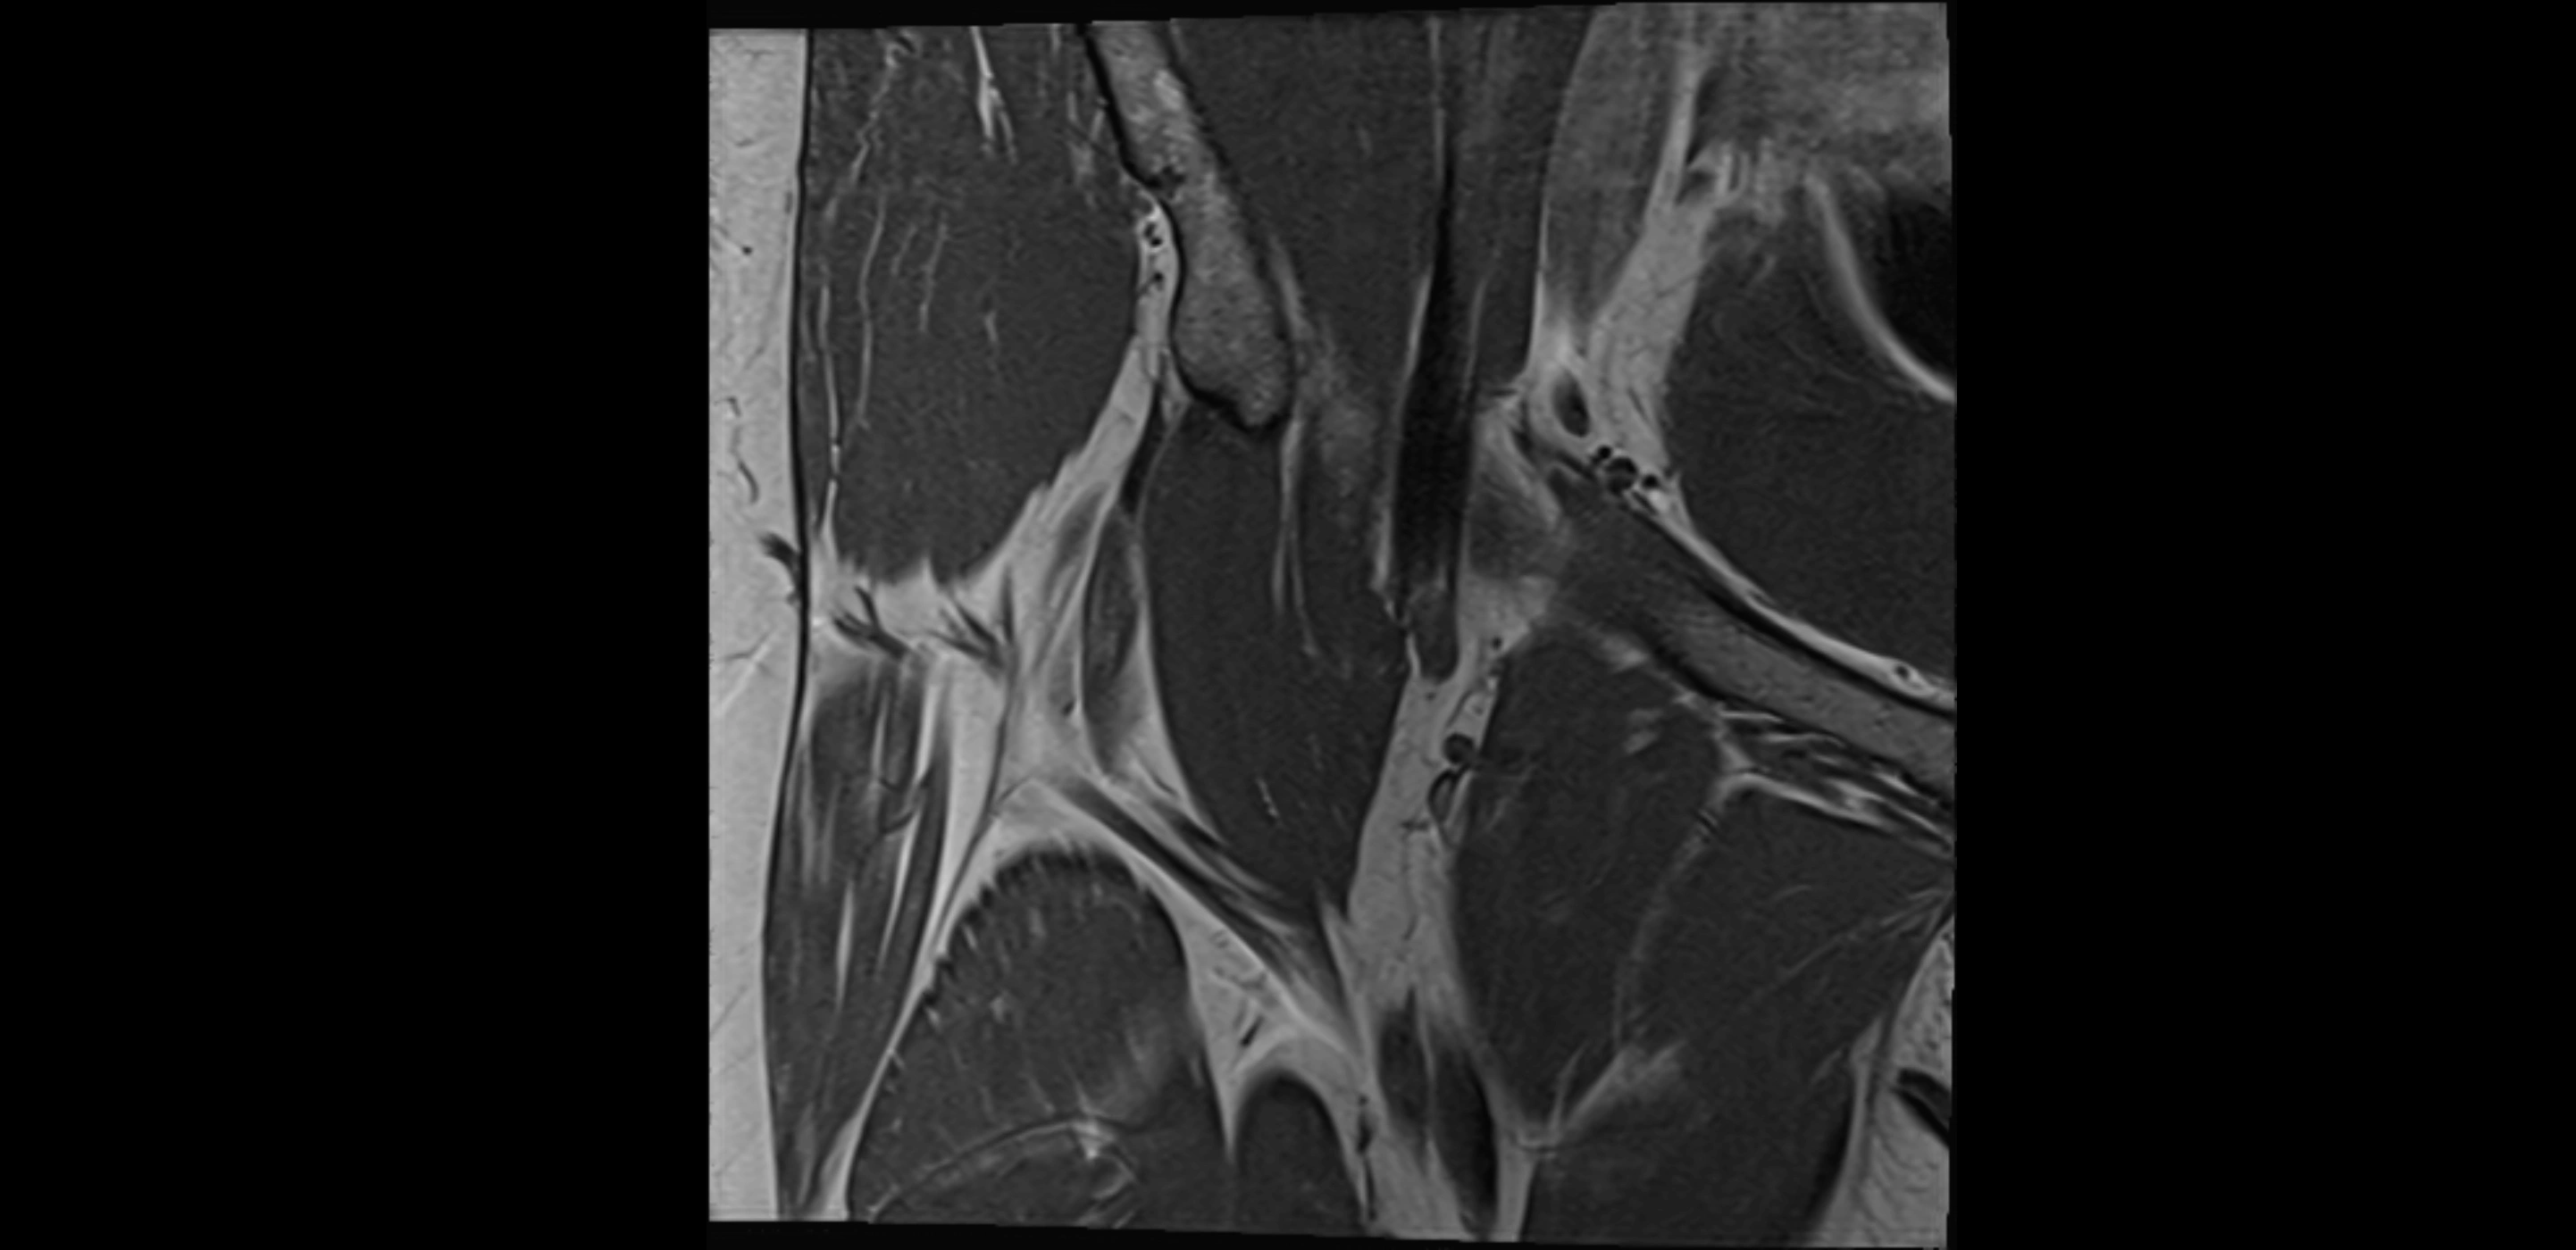

MRI image

image